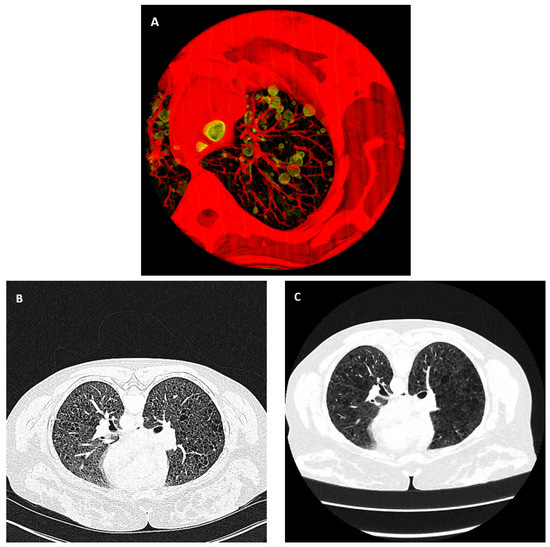

2.4. Automated Cyst Segmentation